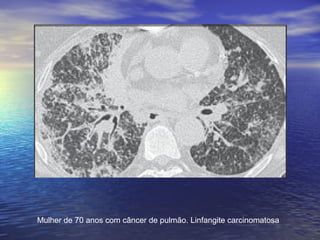

Mulher de 70 anos com câncer de pulmão. Linfangite carcinomatosa